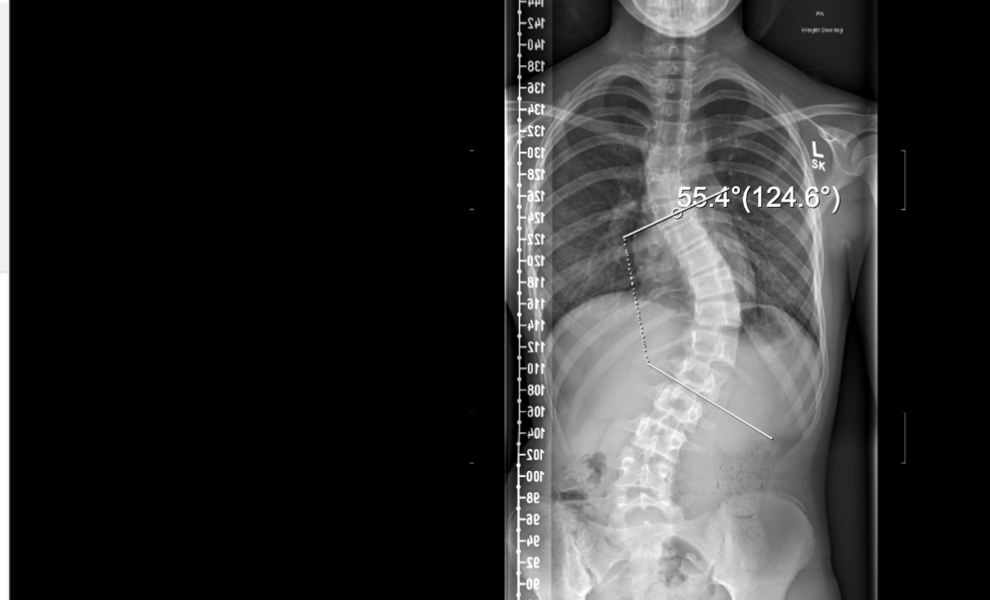

Nancy was Diagnosed with a Significant Scoliosis around 12 Months ago, age 12 by a Physio at her Dance School. My daughter Nancy was diagnosed with a significant scoliosis around twelve months ago…